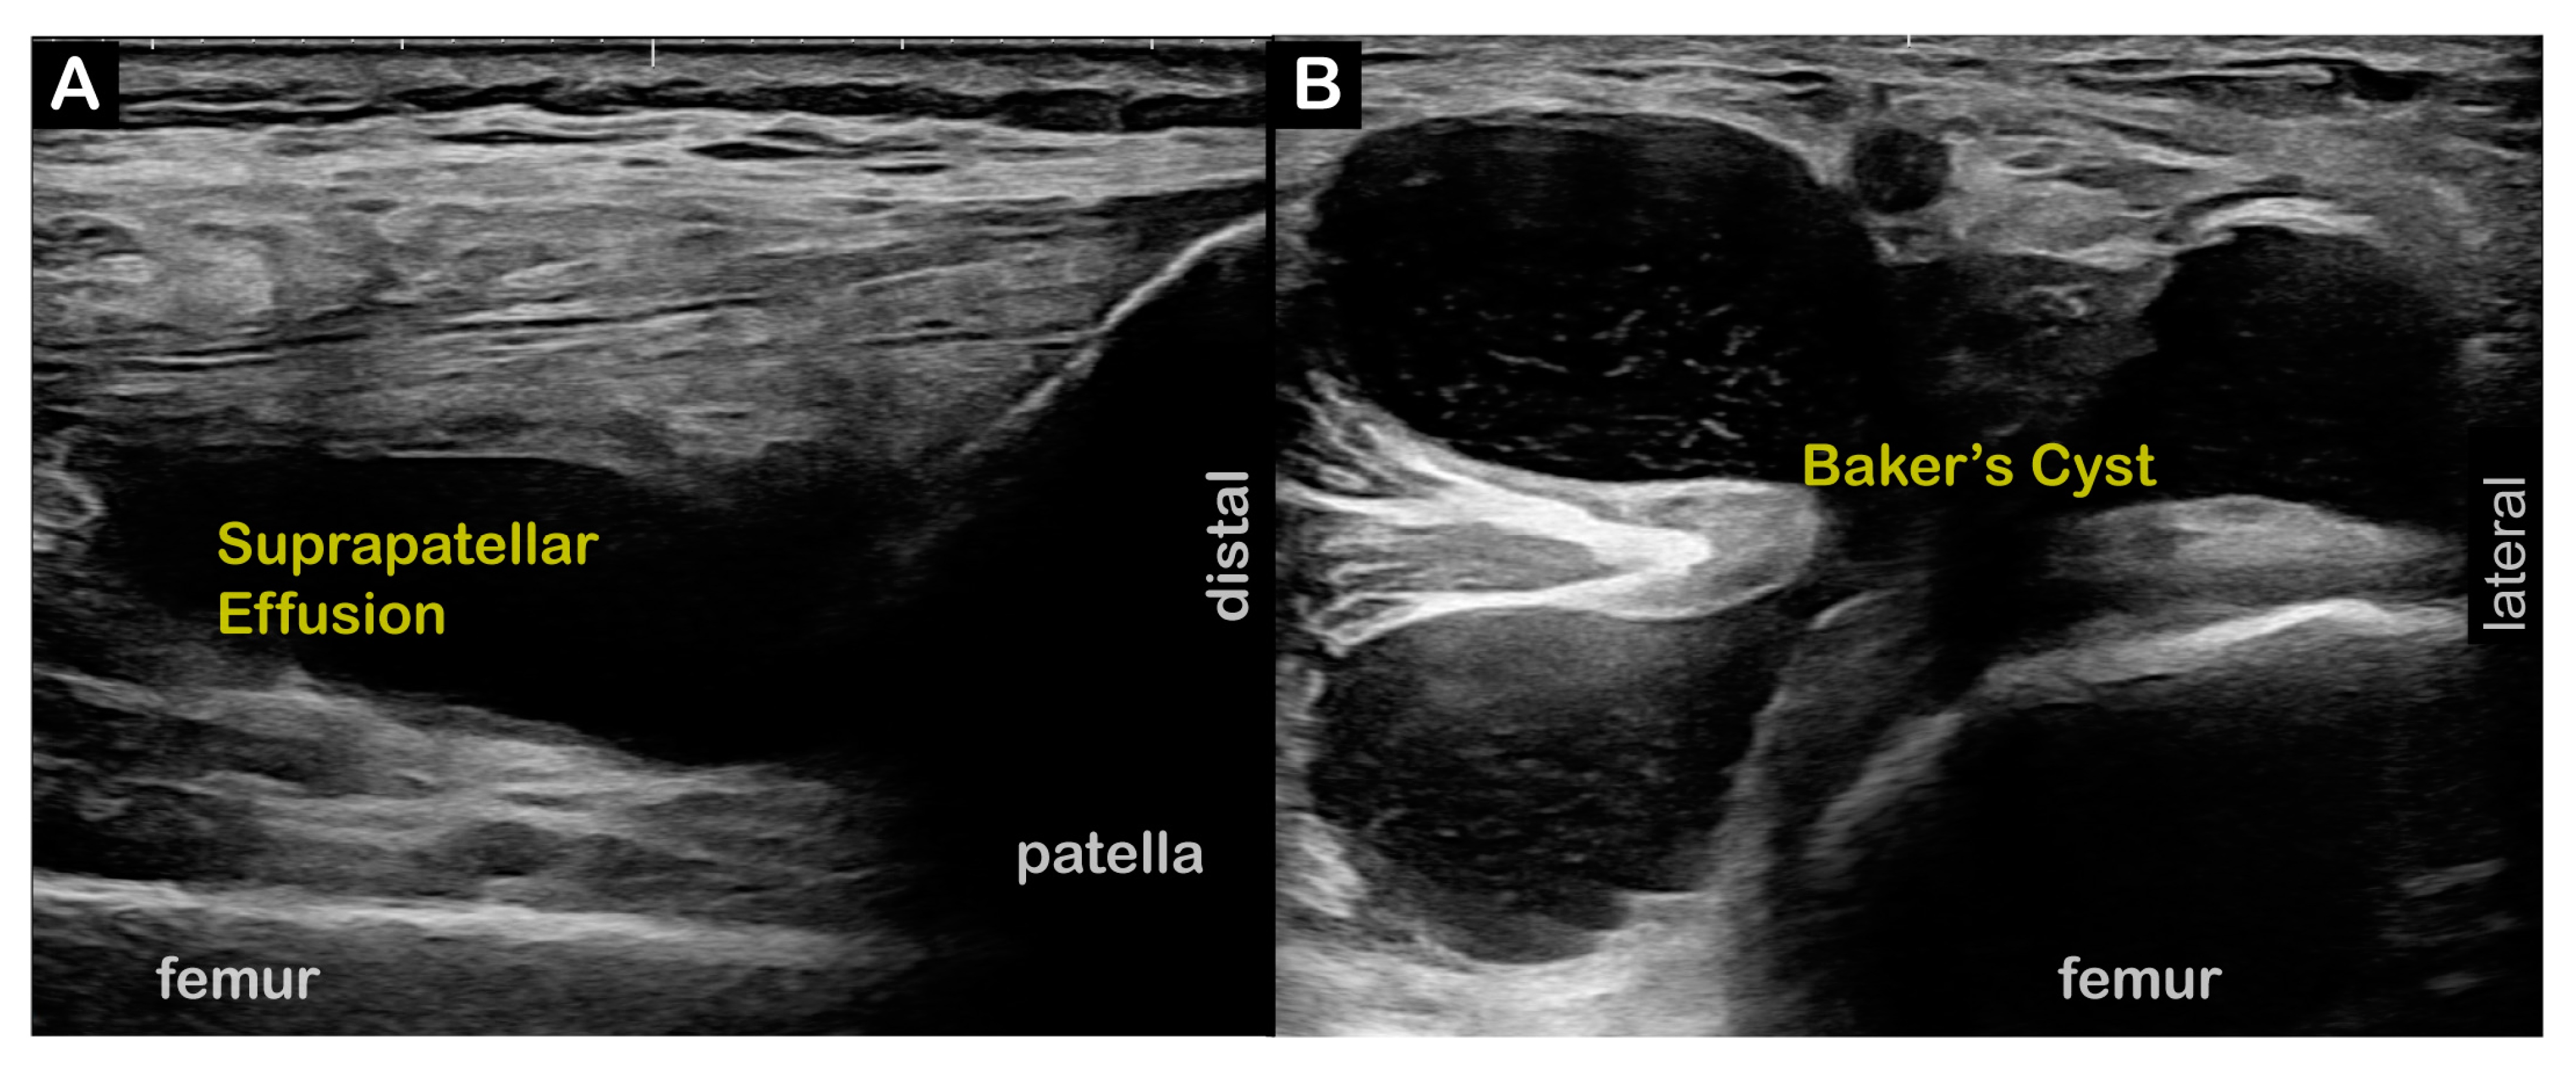

| Diagnostic US |

| Diagnostic US | |